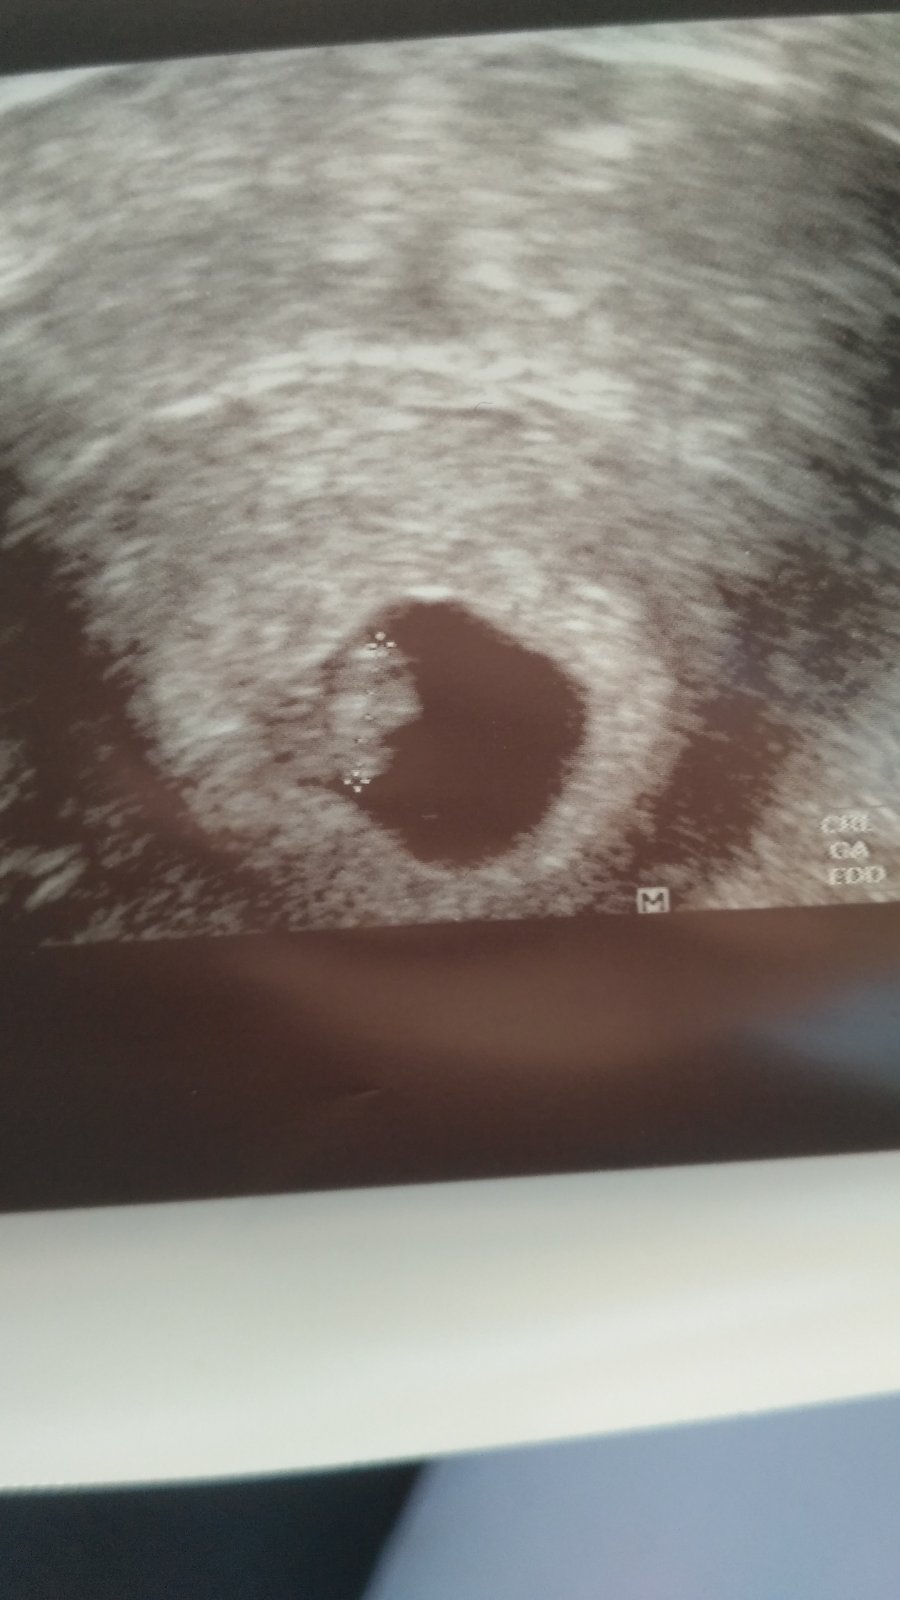

Podarilo sa! Som tehotná - 1 trimester

Ahojte dievčatá, vytvorila som túto skupinu pre tie z nás, ktorým sa vyplatili mesiace trápenia s IVF a konečne sme sa prehupli do vytúženej kategórie - tehotná. Aké máte pocity, obavy, aké cítite zmeny o tom všetkom tu!